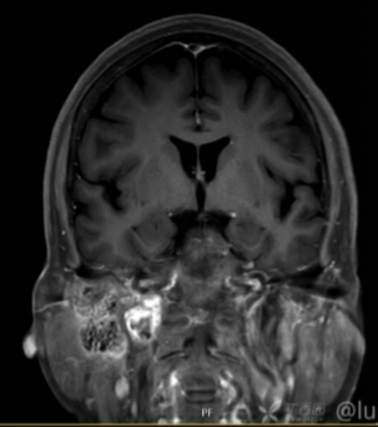

(2023-05-15 10:00,本院)行磁共振(颅脑)检查提示:右侧乳突区异常信号,考虑恶性、软骨来源肿瘤,软骨肉瘤可能性大。(集体讨论意见);脑内散在多发缺血灶。

(2023-05-12 10:15,本院)行CT(颅脑)检查提示:右侧颞骨广泛骨质破坏,伴巨大软组织肿块,性质待定,考虑肿瘤性病变,颈静脉球瘤?软骨源性肿瘤?请结合临床及病理进一步明确。